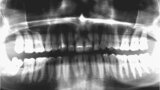

Fig. 2. Situación inicial, radiografía panorámica (2015).